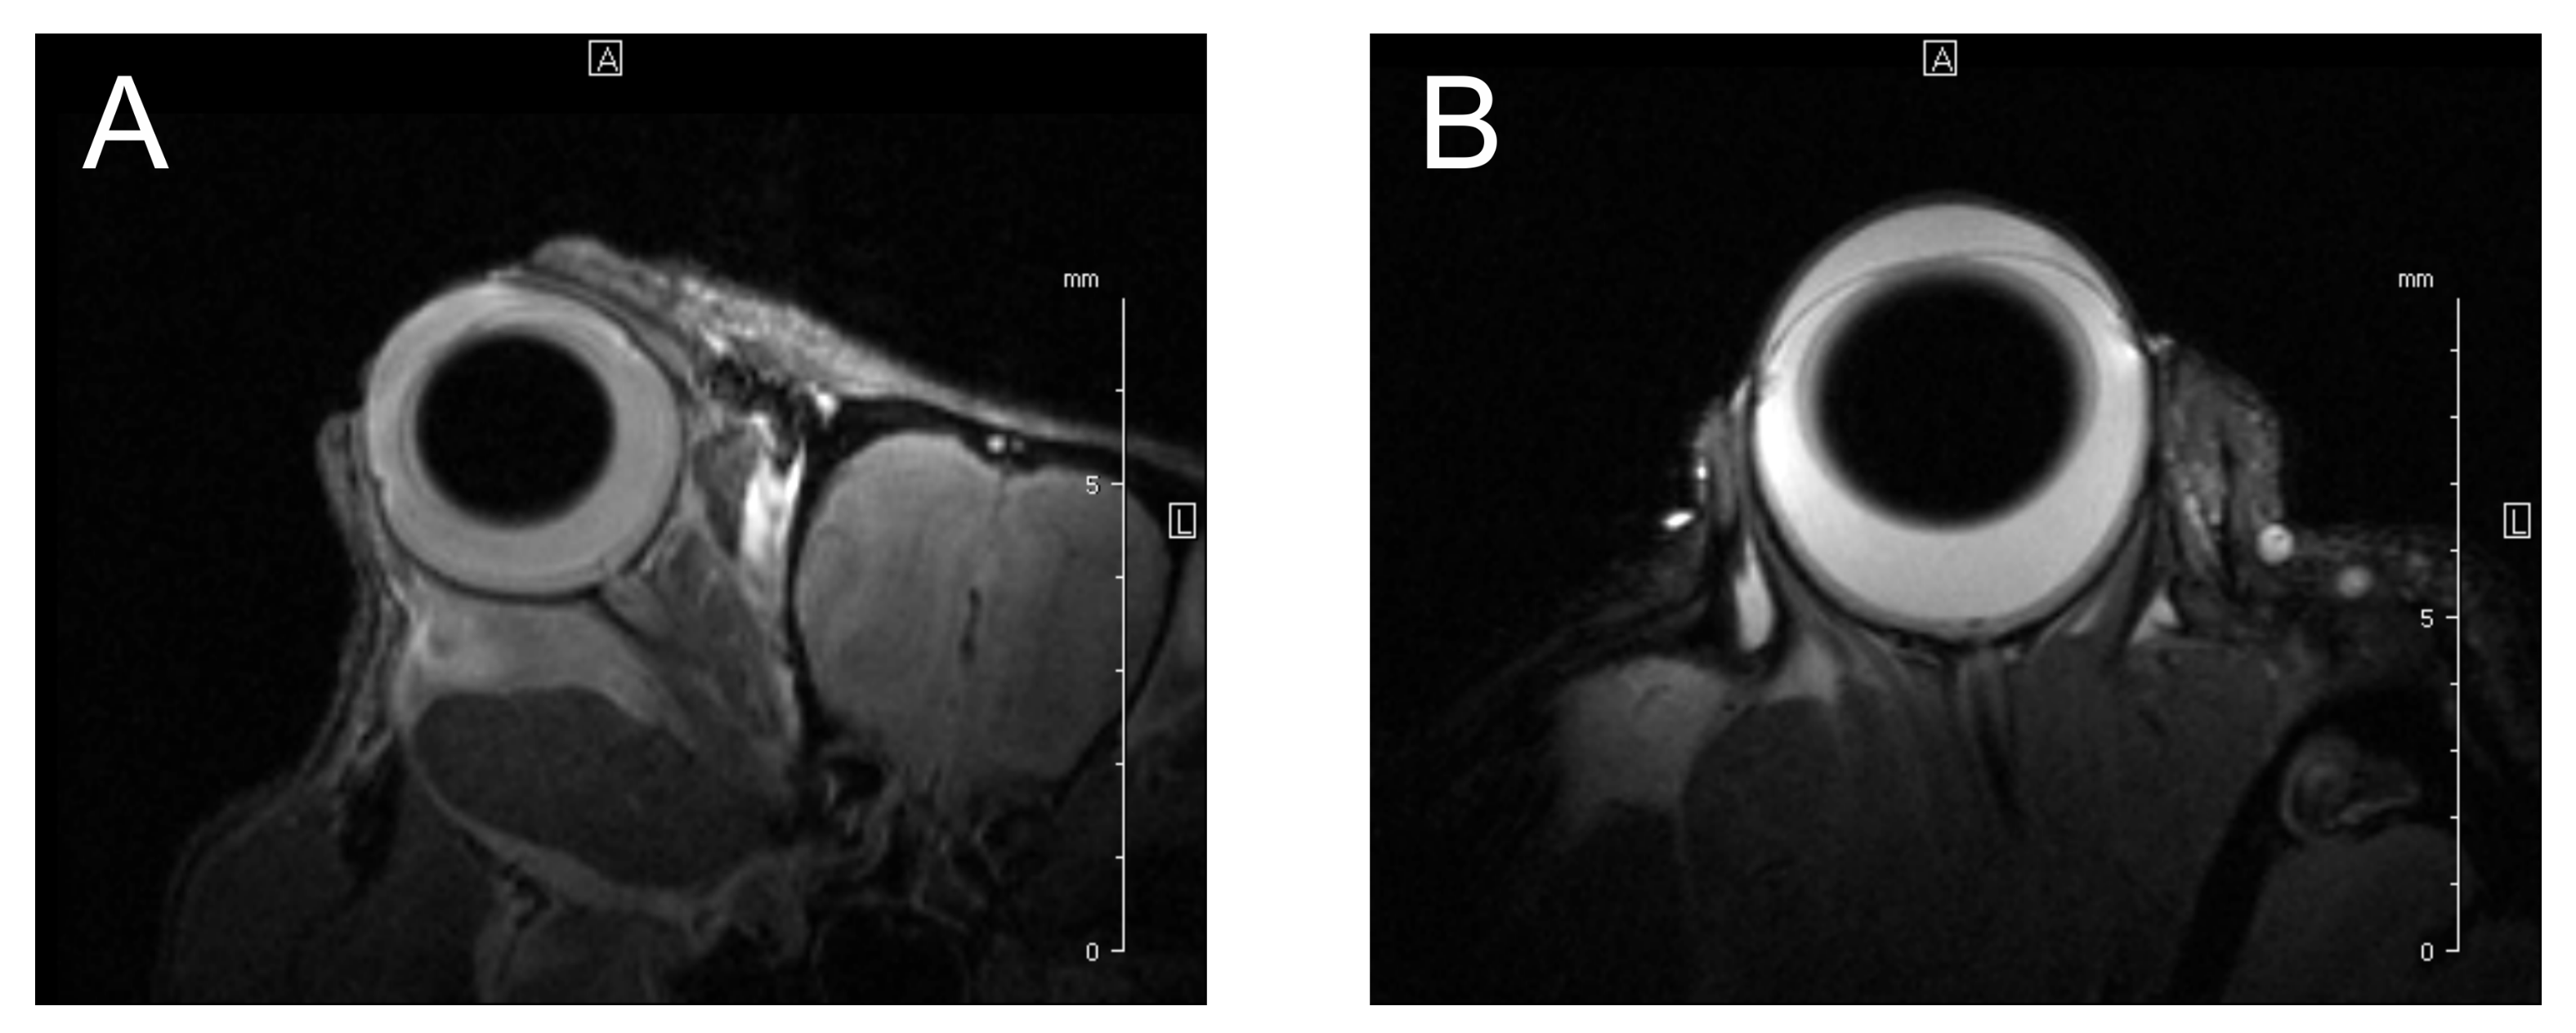

2.5. Magnetic Resonance Imaging

| MRI | noninvasive without exposition to ionizing radiation favorable soft tissue contrast a convenient method to visualize intra- and extraocular involvement good to measure the tumor used to detect distant metastases, especially in the liver used in choosing the therapeutic method | difficult to distinguish amelanotic melanoma from melanotic ones choroidal metastases could mimic a uveal melanoma difficult to distinguish tumor from vitreous hemorrhage movement artifacts relatively long duration time of approximately 20 min the relatively high price of EUR 200–EUR 1000 | 3T MRI 800 µm, 7T 500 to 650 µm, and 32 μm obtained by 9.4T MRI |